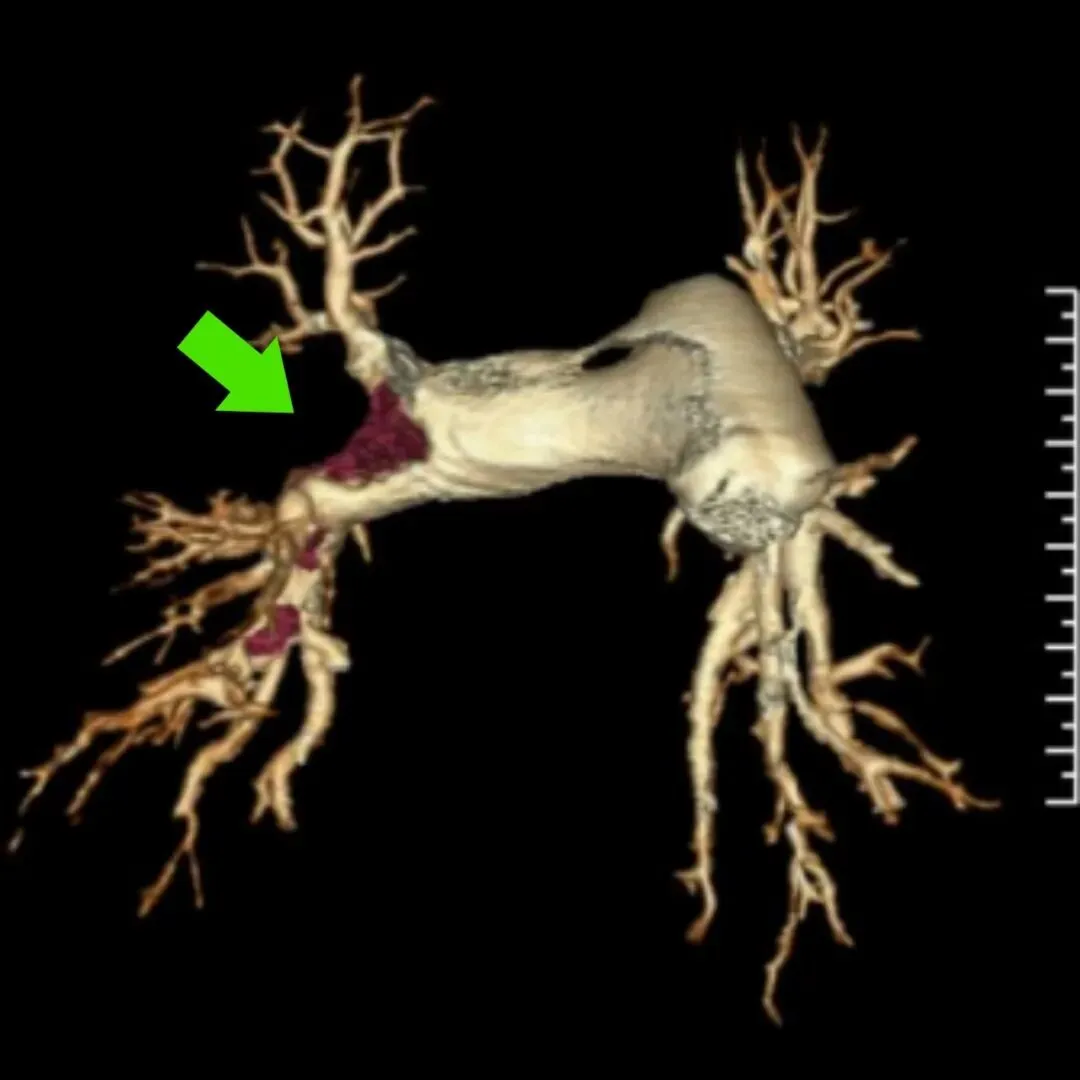

②影像学检查:CT肺动脉造影(CTPA)扫描速度快,图像可以多方位重建,能清晰显示血栓位置,是确诊肺动脉栓塞常用的方法。影像表现如图所示:

右肺动脉栓塞